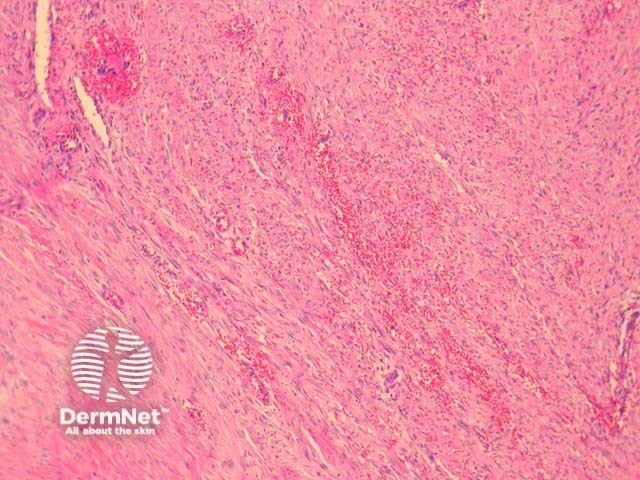

The tumour is composed of haphazardly arranged mass of spindled and plump cells which is often compared to tissue culture. The cells are set in a fibromyxoid stroma. Some typical mitoses are commonly seen. There may be numerous red blood cells (figure 2), and chronic inflammatory cells. Proliferative fasciitis is a well recognized variant and is composed of epithelioid cells which resemble ganglion cells (figure 3).

Figure 2